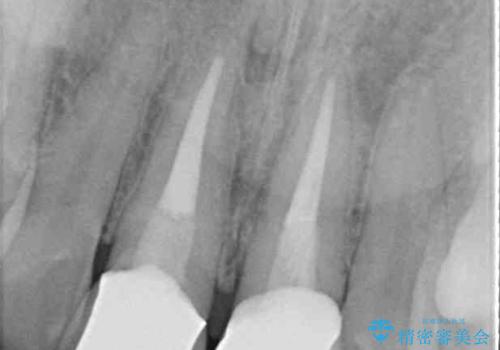

- 前歯のクラウン付近の歯肉が黒く見えることを気にして来院された患者様です。

10年以上前に根管治療を行っており、その際にはラバーダムを使用してしっかりと治療を行っていたとのことで、今回は根管治療は行わずに土台のみを作り替えた上で、オールセラミッククラウンにて補綴治療を行うこととしました。